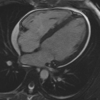

The Society for Cardiovascular Magnetic Resonance (SCMR) is an international society focused on the research, education, and clinical application of cardiovascular magnetic resonance (CMR). The SCMR web site ( https://www.scmr.org ) hosts a case series designed to present case reports demonstrating the unique attributes of CMR in the diagnosis or management of cardiovascular disease. Each clinical presentation is followed by a brief discussion of the disease and unique role of CMR in disease diagnosis or management guidance. By nature, some of these are somewhat esoteric, but all are instructive. In this publication, we provide a digital archive of the 2019 Case of the Week series as a means of further enhancing the education of those interested in CMR and as a means of more readily identifying these cases using a PubMed or similar search engine.